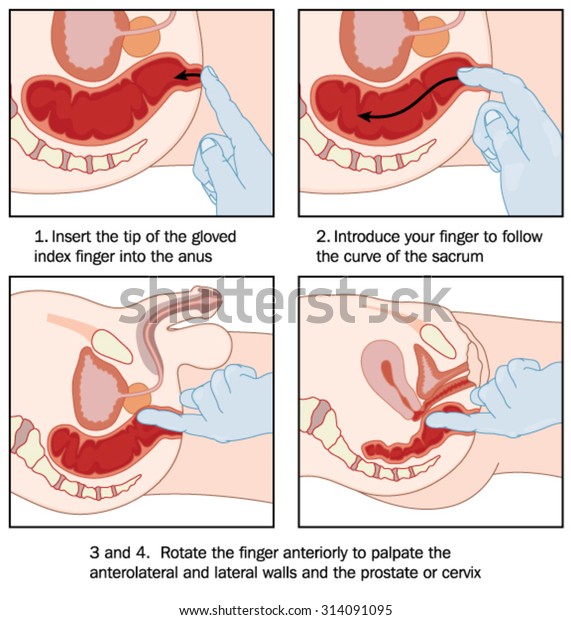

骨盤腔と検査官の指の断面を示す男性と女性の両方の患者の直腸検査法 のベクター画像素材 ロイヤリティフリー

前立腺癌の検査